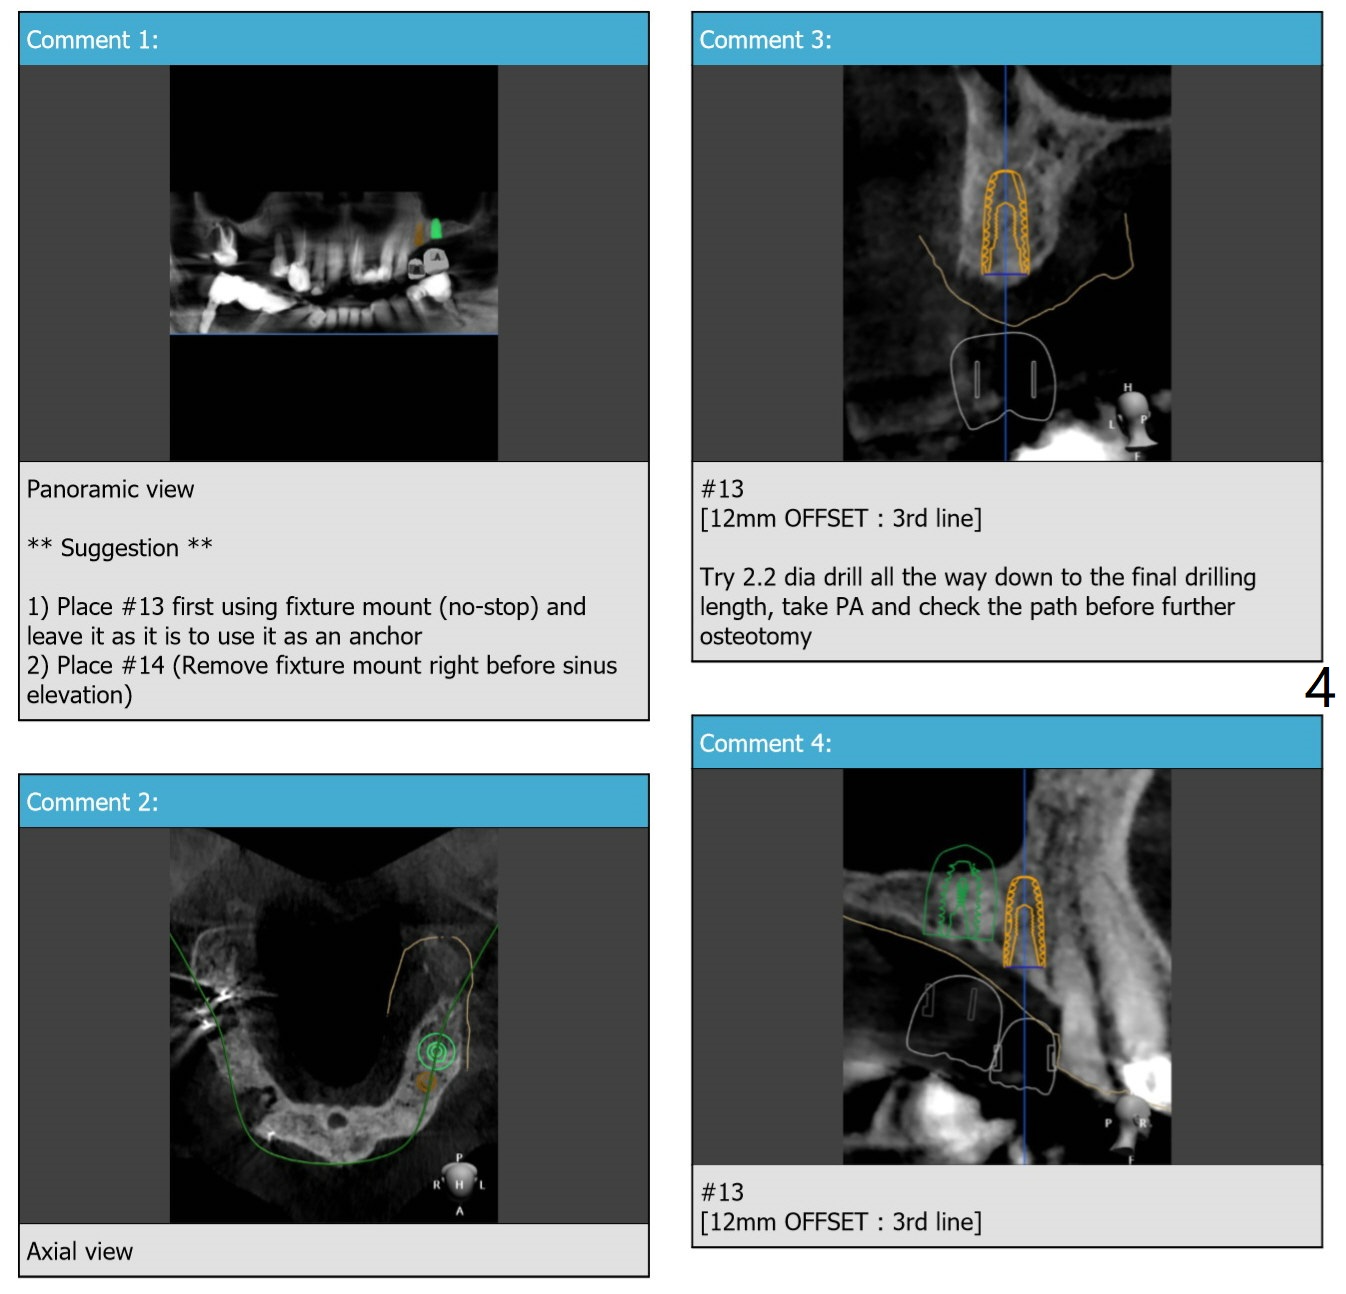

Uneven Bone

A 73-year-old man

Return to Upper Arch Immediate Implant,Trajectory Xin Wei, DDS, PhD, MS 1st edition 07/02/2019, last revision 08/06/2019